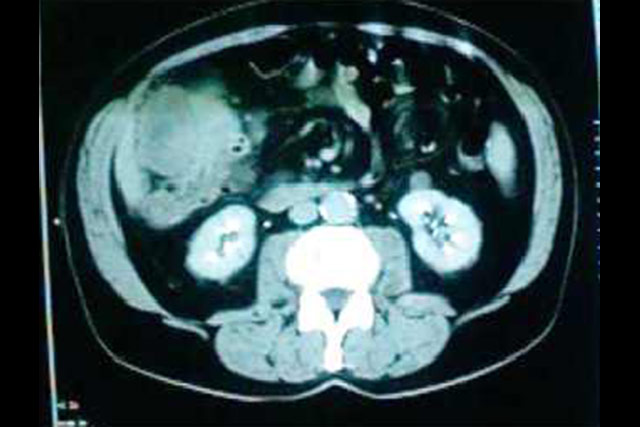

Tumoração de colon com

implantação em grande epiplon.